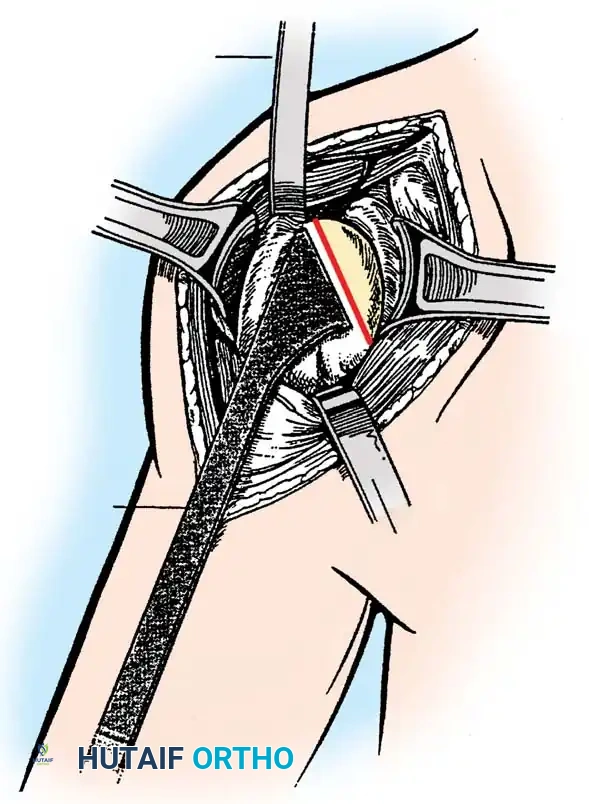

4. Glenoid Preparation

Excellent exposure is critical. Release the inferior capsule completely from the glenoid rim.

* Identify the center point of the glenoid.

* Perform concentric reaming to correct version and create a bleeding bone bed.

* Pitfall: Avoid excessive reaming, which penetrates the dense subchondral bone plate and enters the weaker cancellous vault, leading to catastrophic early subsidence.

Cement the all-polyethylene glenoid component using pulsatile lavage, meticulous drying, and pressurization techniques.